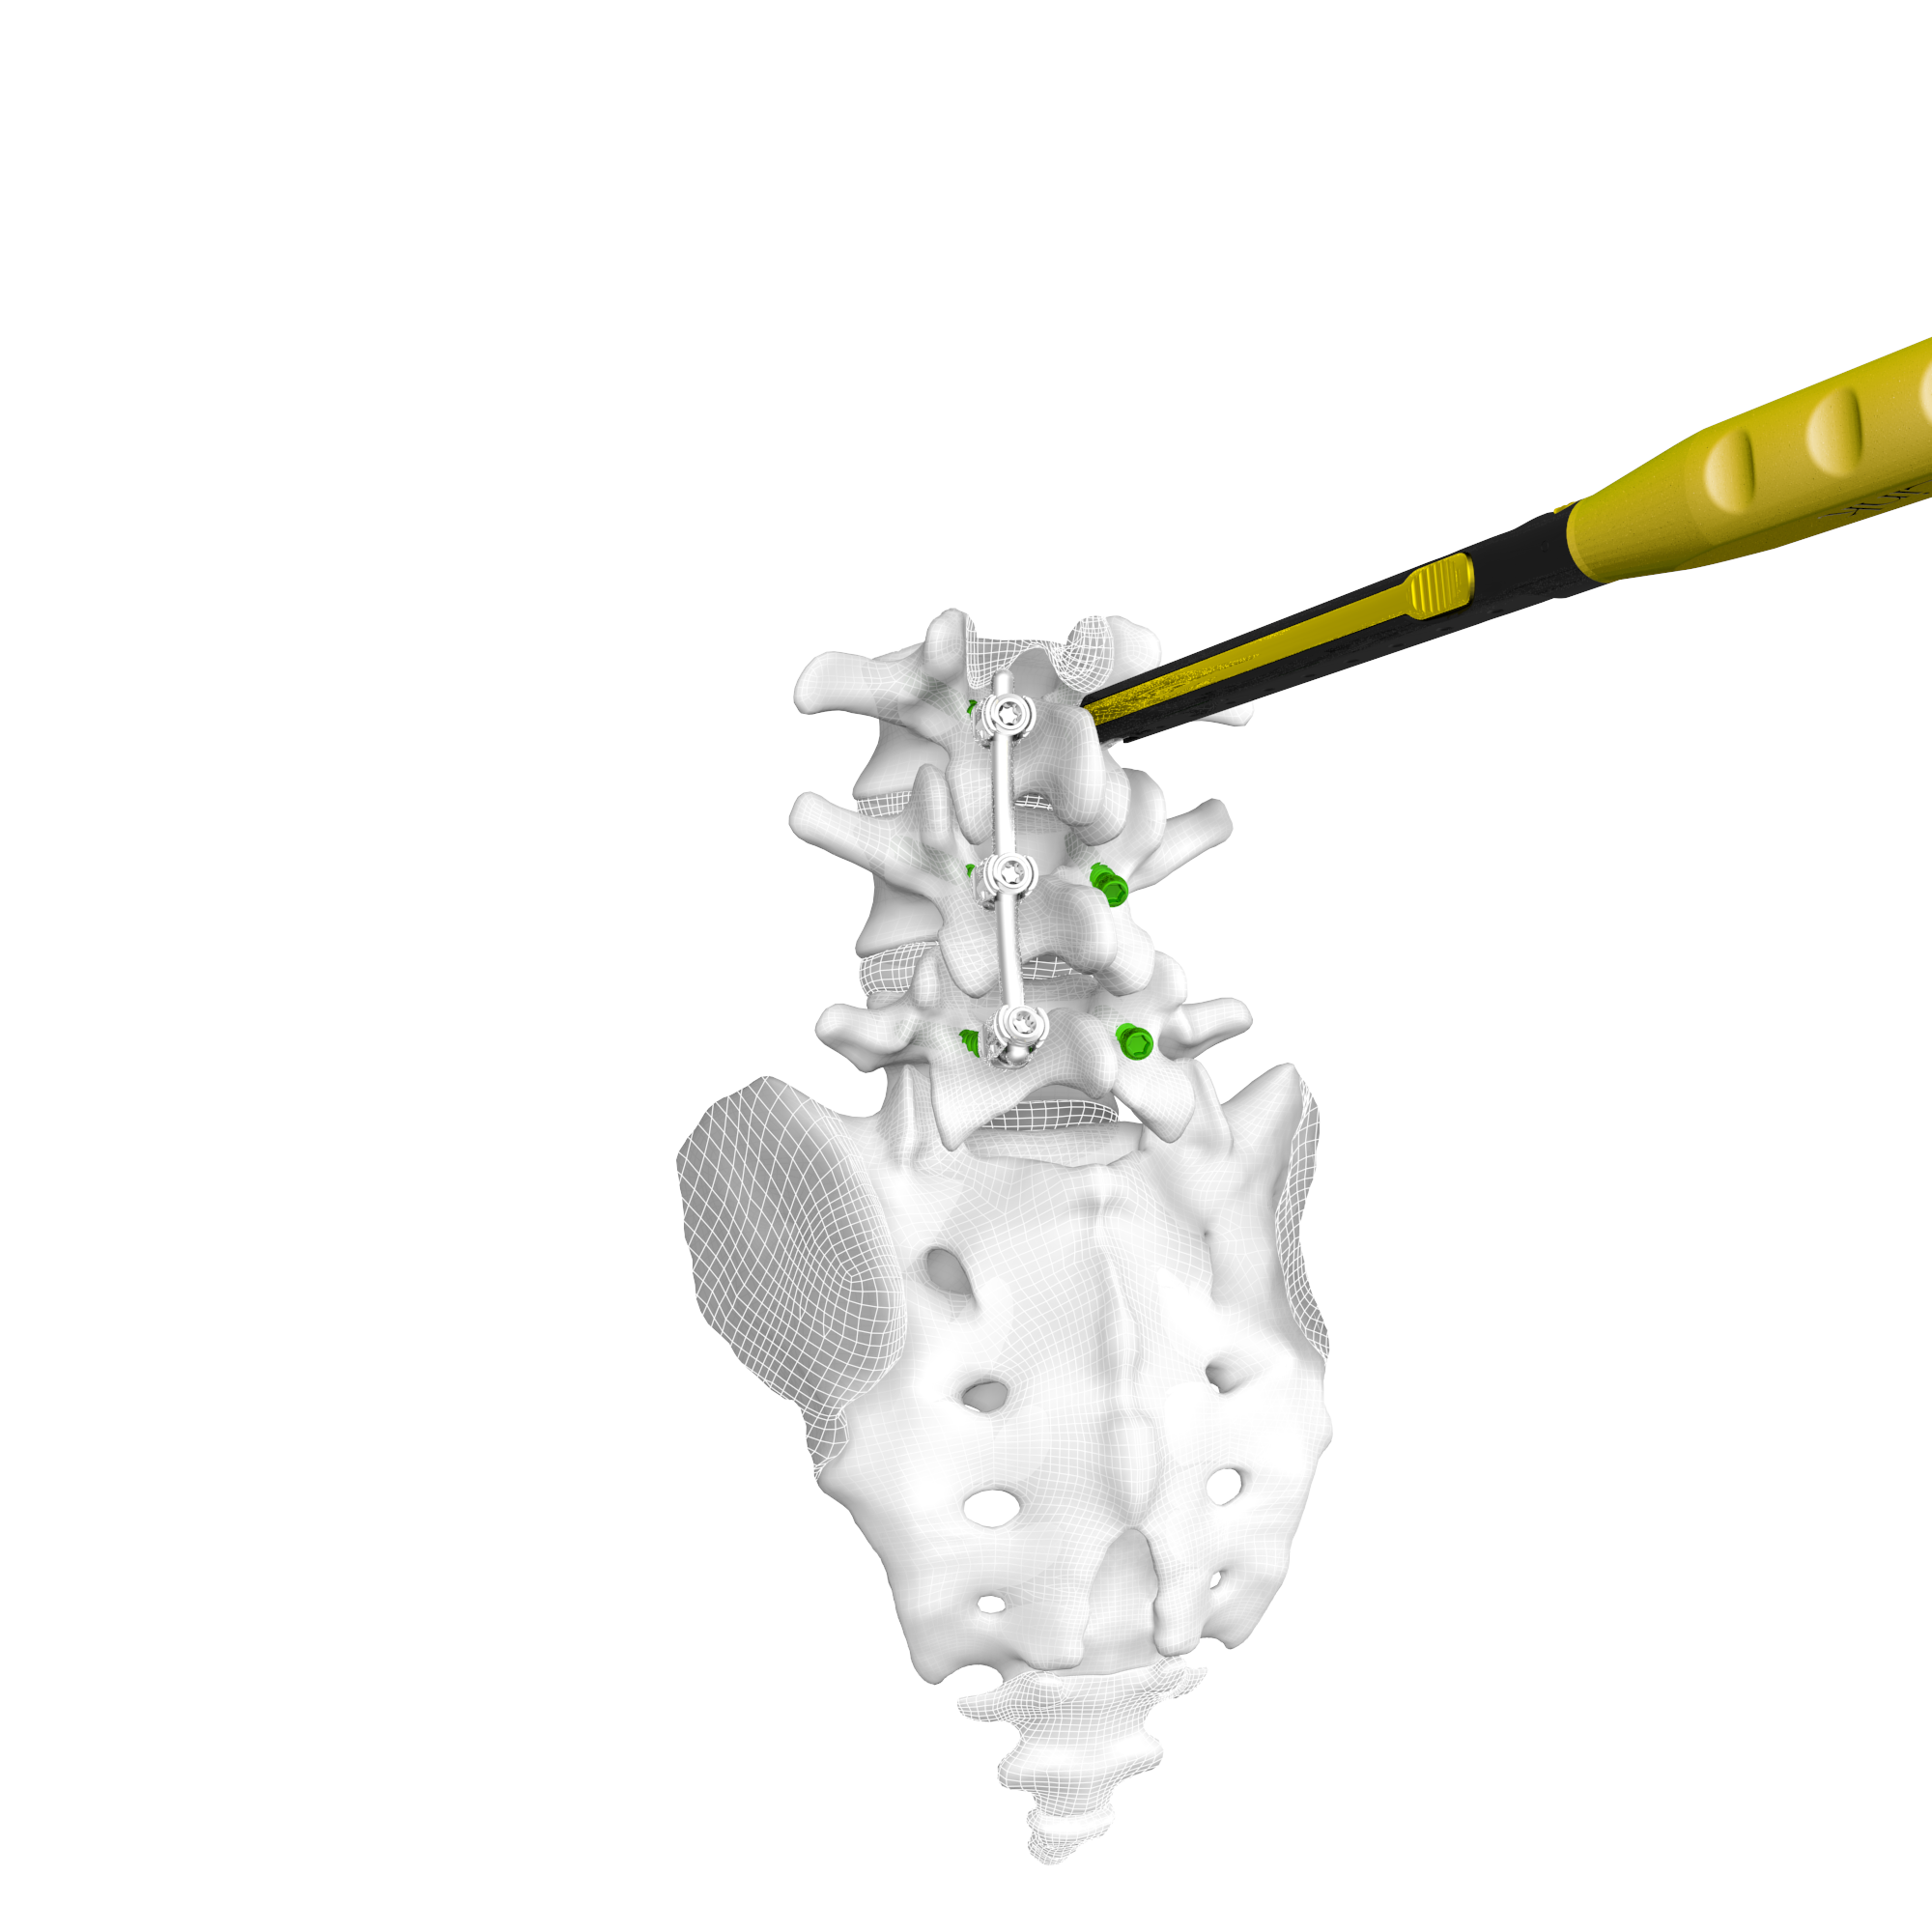

CentraFix® Midline Fixation System

The CentraFix Midline Fixation System is a posterior thoracolumbar pedicle screw system designed for a midline approach with a medial to lateral cortical bone trajectory. The system contains modular tulip heads and screw shanks designed specifically for cortical fixation. CentraFix allows for unmatched intraoperative visualization and surgical flexibility.

Product Features

- Low-profile, anatomic tulip heads allow for reduced tissue disruption without compromising strength

- Modular tulip heads allow for increased visibility and simplified distraction

- Self-drilling, self-tapping cortical screw threading provides easy screw starting in the intended trajectory

- Set screws designed to minimize tulip splay and reduce cross-threading

- Tulip heads accept 4.75mm or 5.5mm diameter rod options